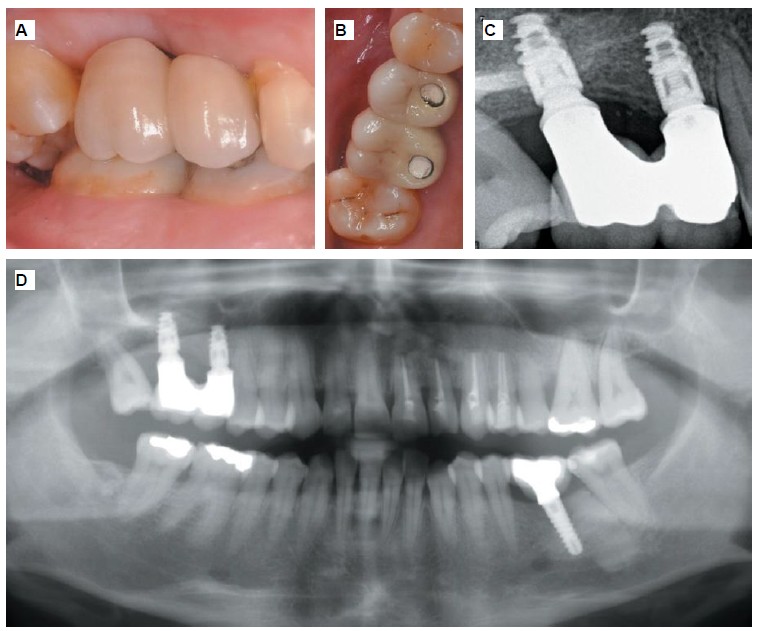

Métodos: Se llevó a cabo un caso clínico en una paciente de 40 años con fracaso de restauración fija dentosoportada en el incisivo central superior izquierdo, asociado a caries radicular subgingival con mal pronóstico restaurador. Tras la evaluación clínica y radiográfica, se indicó la exodoncia atraumática del diente afectado. Inmediatamente después, se realizó la colocación de un implante postextracción. El defecto periimplantario (gap) fue rellenado con un xenoinjerto óseo bovino. De forma simultánea, se llevó a cabo un injerto de tejido conectivo con el objetivo de optimizar el volumen y la estabilidad de los tejidos blandos periimplantarios. Se procedió a la colocación de una restauración provisional inmediata atornillada, diseñada para preservar el perfil de emergencia y guiar la cicatrización de los tejidos periimplantarios. Tras un periodo de cicatrización de cuatro meses, se colocó la restauración definitiva atornillada.

Resultados: El seguimiento clínico y radiológico evidenció una correcta osteointegración, estabilidad de los tejidos periimplantarios y un resultado estético satisfactorio, mantenido a los cuatro años.